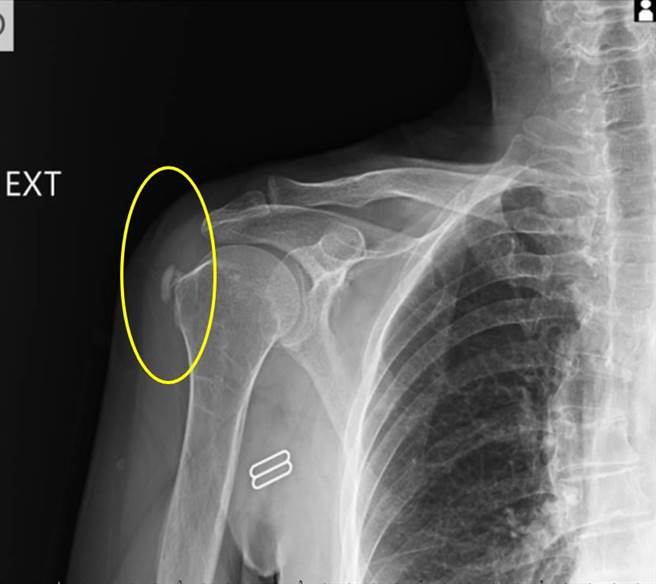

今年67岁的陈女士肩膀经常疼痛,今年1月到丰原医院挂復健科门诊,理学检查发现手臂上抬与内转时会因严重疼痛而无力,当天安排X光检查后,发现除有旋转肌肌腱炎外,还出现严重钙化,就是肩关节钙化性肌腱炎;建议她除做一般常规復健外,再安排3次的自费震波治疗,一个月后追踪照X光片发现钙化点完全消失,肩关节疼痛与功能都得到大幅度的改善。

丰原医院復健科医师张宪伯说,体外震波对钙化性肌腱炎是种非常有效的治疗方式,根据研究透过3次震波并追踪3个月后,钙化点多能显着变小,甚至有36%病人钙化点可在震波3个月后完全消失;相较于没有復健需要经过3-10年才有1/3的病人会慢慢吸收,打震波的效果快而显着。